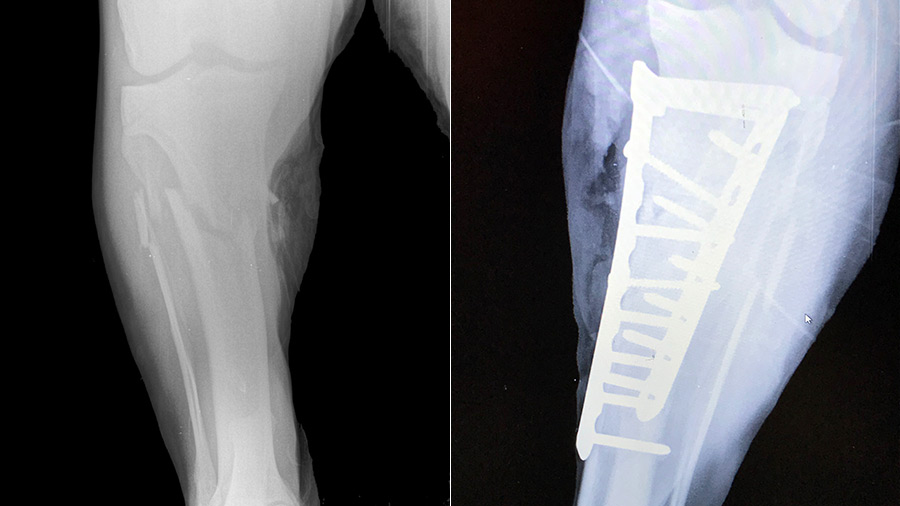

After the patient was sedated with a dart gun, the surgical team—including Bergmann running anesthesia, technicians grabbing necessary supplies and taking intraoperative radiographs, and Gasiorowski and Monaco performing the surgery—had to move fast. The fracture was repaired with bone plates on both the medial (4.5 mm locking compression T-plate) and lateral (4.5 mm narrow locking compression plate) aspects of the tibia. Intraoperative radiographs were used to guide plate and screw placement.

After the surgery, the lioness woke up in a small room with bedding and observation windows, and the zoo veterinarian remained by her side until her vital signs were stable. After an initial period of confinement to limit the patient’s physical exercise, zoo staff began to exercise the lion daily. After 10 weeks, she was back on display at the zoo.

“She has full use of the limb and full range of motion,” Gasiorowski said. “This patient case highlights how universally applicable the AO principles are. Bone is a unique tissue and to achieve optimal results, you need to adhere to these principles.”